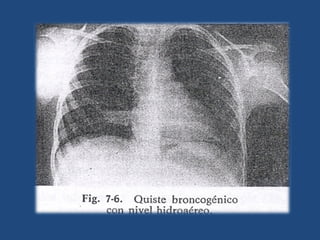

 En el proceso de ramificación bronquial, un fragmento

de esbozo bronquial queda aislado del resto del árbol

bronquial y forma una cavidad esférica, tapizada de

epitelio respiratorio y llena de material mucoide.

 Se distinguen dos tipos:

a) Intrapulmonares. Están dentro del pulmón. Mientras

permanecen aislados del árbol bronquial, son

asintomáticos.

 Tras una infección, pueden abrirse en el árbol

bronquial, con lo que el material mucoide de su

interior, denso, es sustituido por aire, pus o por

ambos.

 Puede aparecer entonces hemoptisis o broncorrea.

 Radiográficamente, la imagen densa se transforma

en una imagen aérea de paredes finas, a veces con

nivel hidroaéreo.

 En raras ocasiones en forma un “quiste en balón”,

cuando la comunicación es valvular, entonces

puede comprimir.